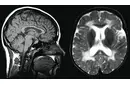

Beyin Dokusu Türleri ve Özellikleri Beyin, merkezi sinir sisteminin en önemli organı olup, karmaşık yapısıyla birçok işlevi yerine getirmektedir. Beyin dokusu, genel olarak iki ana türden oluşmaktadır: gri madde ve beyaz madde. Bu makalede, beyin dokusu türleri ve özellikleri detaylı bir şekilde incelenecektir. Gri Madde Gri madde, beyin yüzeyinde yer alan ve nöron hücre gövdelerinin (soma) yoğun olarak bulunduğu bölgedir. Gri maddenin başlıca özellikleri şunlardır:

Beyaz Madde Beyaz madde, beyin içerisindeki nöronların aksonlarının yoğun olarak bulunduğu bölgedir. Aksonlar, nöronlar arasındaki iletişimi sağlamak için elektriksel sinyaller ileten uzun uzantılardır. Beyaz maddenin özellikleri şunlardır:

Beyindeki gri madde, bilişsel işlevler ve dil becerileri gibi yeteneklerle ilişkilidir. Ancak, gri maddenin artması doğrudan daha fazla dil konuşma yeteneğini geliştireceği anlamına gelmez. Beynin yapısı ve işleyişi oldukça karmaşık ve birçok faktörden etkilenir. Spor yapmak, gri maddeyi arttırabilir ve genel beyin sağlığına katkı sağlayabilir. Ancak zeka seviyesi, sadece gri madde miktarına bağlı değildir; genetik, çevresel faktörler ve diğer beyin yapıları da önemlidir. Spor yapmak, beyin fonksiyonlarını olumlu etkileyebilir ve genel zihinsel sağlığınıza fayda sağlayabilir.